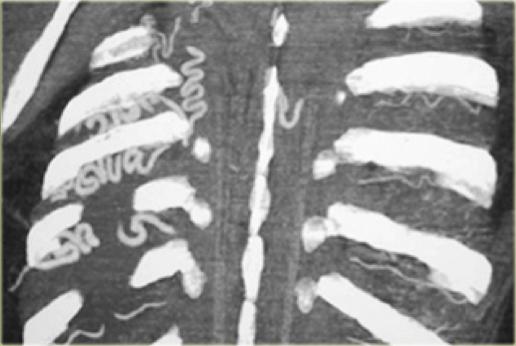

On the left a dominant right arch and a small left arch.

The atretic segment is marked by the arrow.

Notice the four vessel sign.

On a posterior view the interruption is nicely demonstrated.

Remember that there is still a ring, so there is still obstruction.

Another case on the left.

Do not call this a right arch.

It still is a double arch and there is a atretic fibrotic segment on the posterior side of the left arch, that completes the ring.